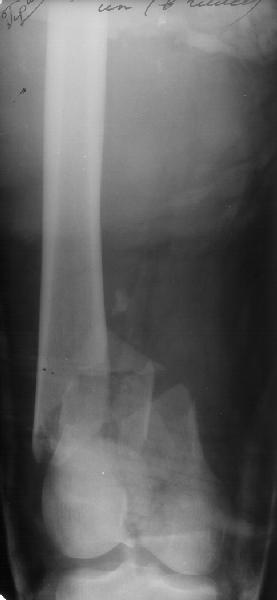

Пациент 27 лет оперирован 2.04.02 через 2 недели после открытого перелома дистального отдела бедренной кости (1 снимок).

Сделан антеградный закрытый интрамедуллярный остеосинтез UFN 11 мм (2 снимок). Вторая нога была ампутирована по месту первичного поступления. Для возможности ранней нагрузки использованы блокирующие винты 6 мм, для чего дистальные отверстия были рассверлены. К двум месяцам начал вставать на костыли, до того занимался разработкой движений в колене. Эти циклические движения в сочетании с тем, что зона концентрации нагрузок приходилась как раз на уровень отверстия, и что перелом открытый и тяжелый и не успел прочно схватиться, привели к перелому стержня 8 июня (3 снимок). Вчера госпитализировали. Такое осложнение у нас впервые. Пока думаем про реостесинтез - вытолкнуть дистальный отломок через дистально, да и через то же отверстие заштифтовать ретроградно. Илиналожить аппарат после удаления центрального отломка стержня, если что-то не будет получаться. Или подумать про пластинку?Заранее спасибо.